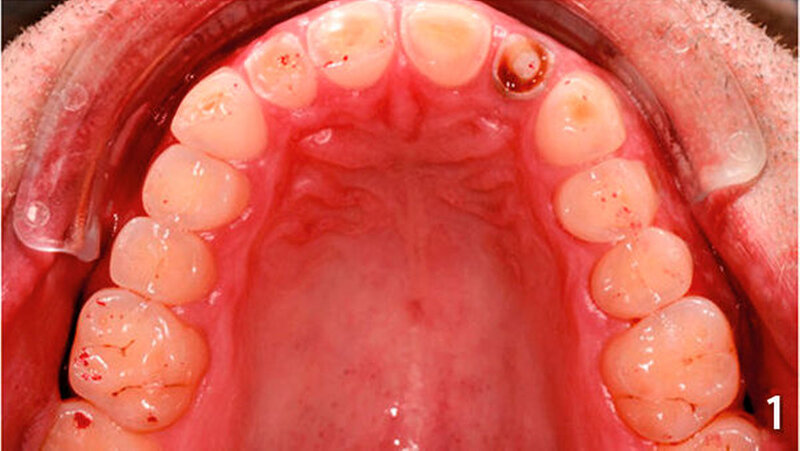

Der Patient wies an allen Frontzähnen sowie an den Seitenzähnen des Unterkiefers starke erosive Defekte auf (Abb. 1-3). Der Patient störte sich vor allem am Erscheinungsbild seiner Oberkieferfrontzähne und dem Engstand im Unterkiefer-Frontzahnbereich. Er wurde über verschiedene Therapiemöglichkeiten ausführlich aufgeklärt und entschied sich für direkte Rekonstruktionen mit Komposit. Im Februar 2016 erfolgte die Versorgung mit Kompositrestaurationen, wie folgt beschrieben.